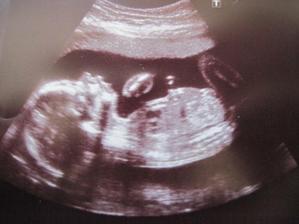

14.9.2009 měla maminka poslední menstruaci a protože je naše Vendulinka ještě maličkatá, sourozence jsme jí chtěli pořídit až tak po jejích druhých narozeninách, tak jsme se s tatínkem v době ovulace chránili, ale jak se ukázalo, tak šťastně nezodpovědně, MS měla zpoždění týden a to už vzhledem k pravidelnému cyklu začínalo být podezřelé a protože byla maminka objednaná na preventivní prohlídku k panu dr. rok od porodu, před plánovanou návštěvou gynekologie si udělala testík a k jejímu překvapení se tam vyšvihla druhá krásná čárečka 🙂 Cestou k dr. to nevydržela a dala testík tatínkovi, který už měl díky zpoždění tušení delší dobu 🙂...........................................Těhotenství podle MS vycházelo akorát na 5+2tt (21.10.2008), na UTZ ale pan doktor bohužel nic neviděl, tak postrašil mimoděložním těhotenstvím, které už máme jednou za sebou a pozval si nás za 14 dní znovu, to ale bylo naprosto nekonečný čekání - kdy začnu krvácet, dostanu šílený křeče do břicha, budu si volat záchranku a řešit, kam dát naši maličkatou holčičku vystrašenou maminčiným stavem, tak jsme se rozhodli svátek................................................................28.10.2009 oslavit tím, že zajedeme do nemocnice, ať máme konečně jasno... Maminka si sbalila věci a čekala, že si jí tam nechají na pozorování, než se mimísek ukáže, jestli je správně v děloze, nebo mimo ni, sestřička neměla pro maminčin strach zrovna ve státní svátek pochopení, tak nám to dala pěkně najevo, ale paní doktorka už byla strašně hodná a milá a hlavně pro nás měla ty nejúžasnější zprávy - miminko je tam, kde má být, podle poslední MS je 6+2tt, podle UTZ 6+0tt, takže všechno je naprosto v pořádku a pokud to dobře dopadne, v červnu budeme mít druhého mimíska - jupíííí 🙂)) Zašli jsme si celá rodina na oběd a užili si krásné odpoledne, kdy nám všem spadl obrovský kámen ze srdíček 🙂........................................................Týden na to - 4.11.2009 (7+2tt) byla maminka na kontrole u svého doktora a další úžasná zprávička je, že našemu prťouskovi tluče srdíčko 🙂)) Drž se, broučku, všechno zvládneme a už teď tu na tebe čeká ta nejbáječnější sestřička na světě a milující rodiče 🙂...................................................................Další kontrola 25.11.2009 - byla to rychlovka, pan doktor jen zkontroloval srdíčko, vypsal žádanku na krev, vyšetřil maminku a to bylo všechno 🙂...................................................................................16.12.2009 NT screening, byl s námi i tatínek, který byl z toho, co viděl, nadšený 🙂 Naše miminko je naprosto v pořádku, má všechno, co má mít, viděli jsme prstíky, chodidla, zorničky 🙂)) Byl to krásný zážitek 🙂)) 30.12.2009 nás čekají krevní tripple testy 🙂 ................................................................................. 12.1.2010 další kontrola, pan doktor nám oznámil, že tripple testy jsou naprosto v pořádku a taky už bylo poznat pohlaví, ani nemusel dr. nic povídat, když najel ultrazvukem mezi nožičky, maminka hned prohlásila, že mimísek je celej tatínek 🙂))................................................... Další velký ultrazvuk v 21tt bude 9.2.2010 🙂)) Máme to za sebou, teda musím říct, že nejhorší okamžiky jsou, když doktor jezdí ultrazvukem po bříšku a delší dobu nic nepovídá, to se honí hlavou takový myšlenky ☹(( Ale hlavní je, že zbytečně, protože je všechno v naprostém pořádku, jsem zdravej, 370g vážící chlapeček a budu se jmenovat pravděpodobně Matýsek (Matěj).............................................. Kontrola 9.3.2010 dopadla opět výborně, Matýskovo srdíčko bije jako o život, roste přesně podle tabulek a během 3 týdnů nás čeká test na cukrovku - brrrrrrrrrrrrrr ☹((, ale když to musí být, tak to zvládneme 🙂 Máme to za sebou - sice každý vpich na druhý až třetí pokus, ale hlavně že se povedlo - výsledky se dozvíme na příští kontrole 6.4.2010 🙂............................................................ 6.4.2010-cukrovku nemáme, jupííí, mimísek se otočil hlavičkou dolů, na pravé straně má páteř a vlevo vesele nakopává maminku do žeber, ale je to zlatíčko 🙂 Na příští kontrole první monitor a velký ultrazvuk 🙂 To bude 27.4.2010..............................................................27.4.2010 - první monitor a poslední velký ultrazvuk, tatínek byl s námi, všechno je v naprostém pořádku, Matýsek má 1900g, tak už je to pořádnej chlap, délka těhotenství odpovídá 31+6, dle poslední MS 32+1, takže i termín porodu souhlasí, od této doby kontrola každý týden, kromě nevolností maminku netrápí vůbec nic a Vendulka už se na brášku moc a moc těší 🙂 Také jsme koupili sourozenecký kočárek Phil&Teds Vibe, tak i tuhle radost máme vyřešenou 🙂 Až nafotíme, tak přidáme fotečky 🙂...................................................... Kontrola 11.5.2010 už tak dobré zprávy nepřinesla ☹ Ten náš prťousek je asi paličák a usoudil, že hlavičkou dolů už byl dost dlouho a otočil se, takže pokud tak zůstane, čeká nás císařský řez, maminka je z toho zklamaná, ale důležité je, aby bylo všechno v pořádku, jen se moc těšila, jak si užije ten krásný pocit 2 společných hodin na sále hned po porodu ve třech, ale holt to zaspí a tatínek jí pak bude všechno vyprávět, co se s naším mimískem dělo ☹ Ale třeba se ještě umoudří a otočí se zase zpátky, uvidíme na další kontrole, která je 25.5.2010 a pak už bude každý týden... Tak Matýsek je paličák s hlavičkou vzhůru, hned po kontrole u gynekologa jsem naběhla do porodnice domluvit si způsob vedení porodu, přes 2 hodiny tam čekala na to, aby mi pan doktor řekl, že na plánovaní je ještě brzy a šla jsem domů - dostala jsem poučení, kde si můžu vybrat, jestli chci rodit císařem, nebo vaginálně, ve své podstatě to tam bylo podané tak, že z těchto dvou rizik si můžu vybrat, jaký je pro mne přijatelnější, nic moc, hlavně jsem dost mimo, protože nevím, jak se rozhodnout, aby to bylo dobře ☹ Ráda bych rodila vaginálně, ale bojím se možných komplikací, které ale může přinést i císařský řez.... A teď babo raď!!!..................................Nakonec jsem se rozhodla pro možnost, která je míň riziková pro miminko, takže na 21.6.2010 máme naplánovaný císařský řez ☹ Co se dá dělat, nemám na to celý život si pak vyčítat, že jsem se rozhodla špatně - já se dám nějak do kupy, ale miminko ohrozit určitě nechci...